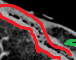

Immunohistochemical staining for Cytokeratin 7, demonstrating the diffusely infiltrating carcinoma in the submucosa, muscular wall, mesenteric adipose tissue, and serosa (Courtesy Dr. V. Penopoulos)